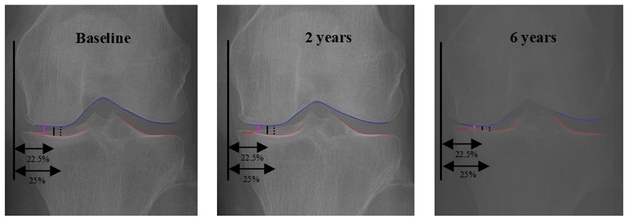

건강보험심사평가원 약제급여평가위원회 심의 결과ⓒ News1 DB관련 키워드혈우병천식혈액암건강보험강승지 기자 국민 63.6% "부정확한 건강정보 경험"…생산자 법적 규제 주문도"AI로 무릎 골관절염 최대 마모 지점 정밀하게 찾아낼 수 있다"